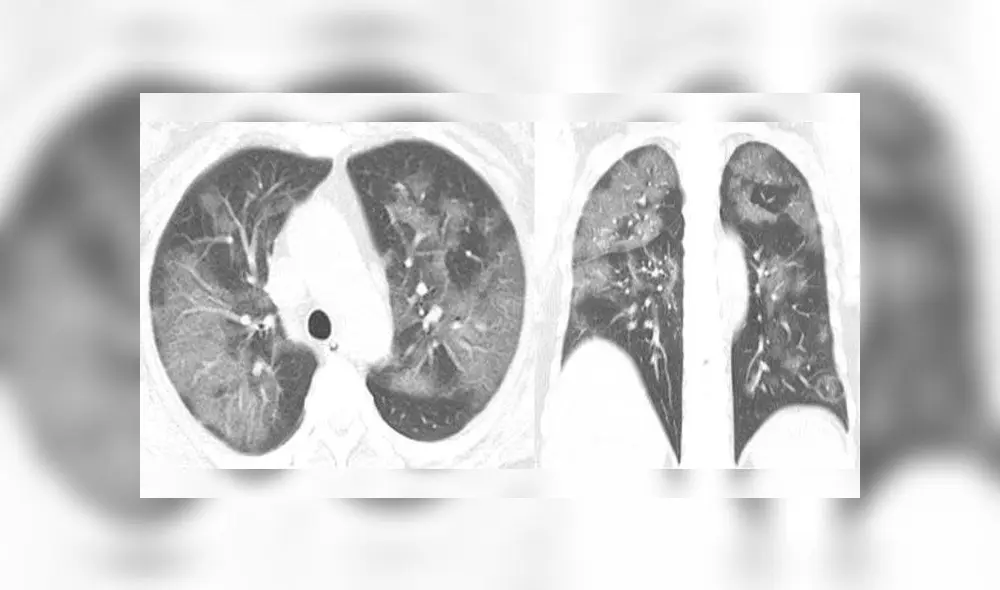

En un grupo de placas se observa la evolución de los pulmones de un hombre de 44 años, procedente de China, quien trabajaba en el mercado de mariscos de Wuhan, donde se cree que surgió el brote. Las tomografías muestran unas manchas blancas en las esquinas inferiores de dichos órganos, conocidas por los radiólogos como “opacidad de vidrio esmerilado”.

Estas anomalías indican un llenado parcial de espacios de aire en los pulmones, de forma parecida a lo registrado en pacientes con enfermedades como el SARS y el MERS.

El hombre ingresó al hospital el 25 de diciembre pasado tras experimentar fiebre y tos por unas dos semanas, siendo diagnosticado con neumonía y síndrome de dificultad respiratoria aguda. Los escaneos grafican como, a medida que pasa el tiempo, el líquido en los mencionados espacios se hace más pronunciado.